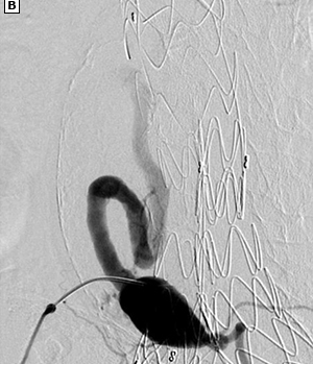

Aneurysmal sac embolization

Trans-vessel Approach

Transcaval

Transarterial perigraft

Transarterial transgraft

Direct Sac Puncture Approaches

Percutaneous translumbar

Percutaneous transcaval

Percutaneous transabdominal